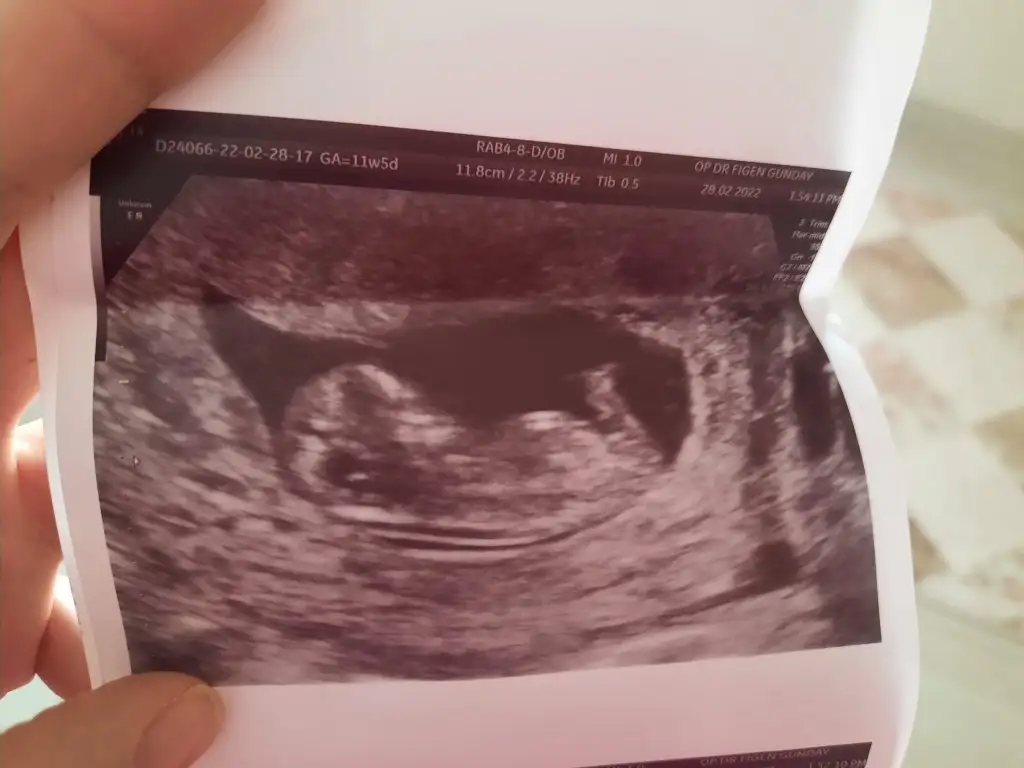

Ya kuzu evet isim yazıyor ya üste ama kırptım bak atıyorumUltrason da isim mi yaziyor

Ahhh tipini seveyim maşallah tam bir bebekYa kuzu evet isim yazıyor ya üste ama kırptım bak atıyorum

Ya onu soracaktım burnunun çok içten ölçmüş doktor 5 mm civarı çıktı bana çok büyük geldi, babası laz ondan mı kiBurnunu ıssırabilirmiyim

Olabilir benziyoda sanki laz burnunaYa onu soracaktım burnunun çok içten ölçmüş doktor 5 mm civarı çıktı bana çok büyük geldi, babası laz ondan mı ki

Sata göre 12+2 ama 12+5 çıktı canım ahahhaha bende çok şaşırdım canım pipişeKuzum gerçekten pipi çok net

12+5 çıktı canımAy nasıl bariz belli canım. Sağlıkla doğsun inşallah.Senin bugün kaç hafta kaç günlüktü bende cumartesi gidicem inşallah tahmin yapar banada İkili test için kan verdin mi ense ölçümü falan yaptı mi?